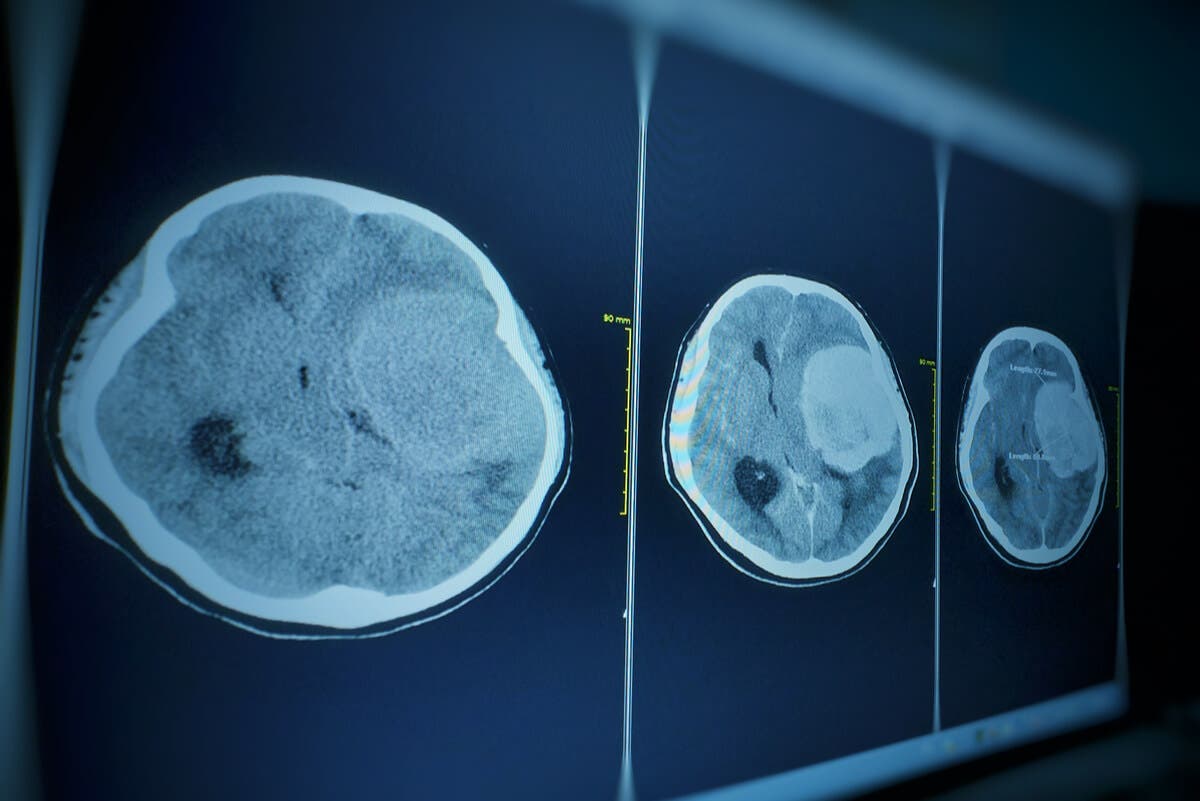

El meningioma es un tumor que, frecuentemente, es benigno. Se produce en el tejido aracnoideo de las meninges, es decir, las membranas que recubren el cerebro y la médula espinal. Según el Instituto Nacional del Cáncer (NIH), este tipo de neoplasia primaria es el proceso tumoral más común del sistema nervioso central.

Es curioso saber que los tumores pequeños (de dos centímetros o menos) suelen ser descubiertos durante las autopsias de los pacientes, pues no generan una sintomatología clara. Los que presentan un tamaño mayor, en cambio, se pueden manifestar de diversas formas. Algunas de ellas son las siguientes: